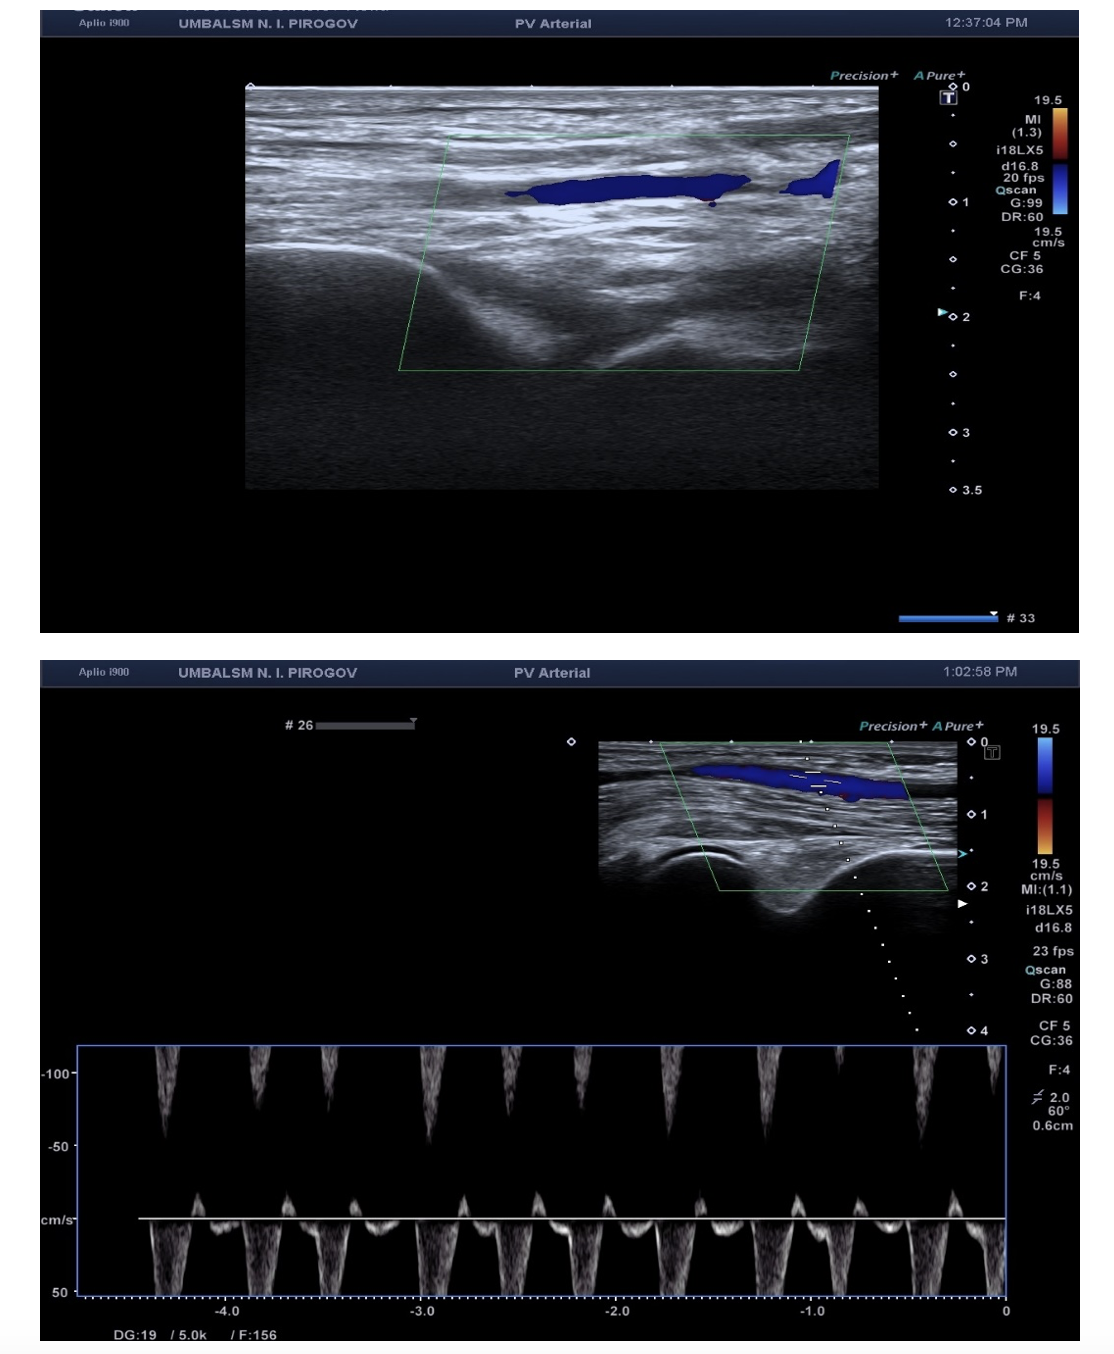

The patient was discharged after 3 days. She returned 15 and 30 days later for a planned Doppler sonography, which objectified the preserved result of the EVT of the right axillary, brachial, radial, femoral, popliteal, and posterior tibial arteries (Figures 13A-C).